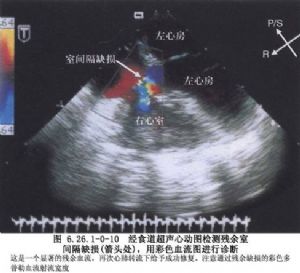

室間隔缺損的大小變異很大,按其口徑臨牀上大致可分爲大、中、小三型。大型室間隔缺損的口徑可以相當於或稍小於主動脈開口,因此右室壓力可接近於體循環壓力。中型室間隔缺損,又稱“限制性”室間隔缺損,其口徑約爲主動脈口徑的1/3~2/3,這類缺損可造成右室收縮壓升高,有的可高達左室收縮壓的50%,兩心室間有壓力階差存在;肺循環和體循環血流量比值上升到2~3.5倍。小型室間隔缺損,是指口徑小於主動脈口徑的1/3,右室收縮壓一般無明顯升高,肺循環和體循環血流量比值<1.75(圖6.26.1-0-8~6.26.1-0-12)。